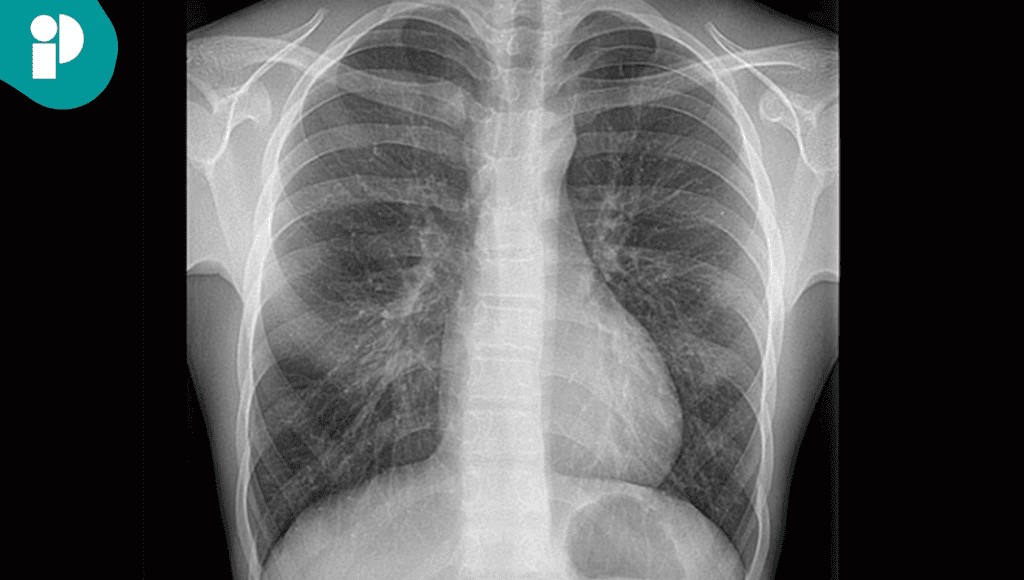

Los estudios iniciales, incluyendo electrocardiograma, radiografía de tórax y análisis de laboratorio, no mostraron alteraciones significativas. La tomografía computarizada evidenció únicamente edema pulmonar leve.